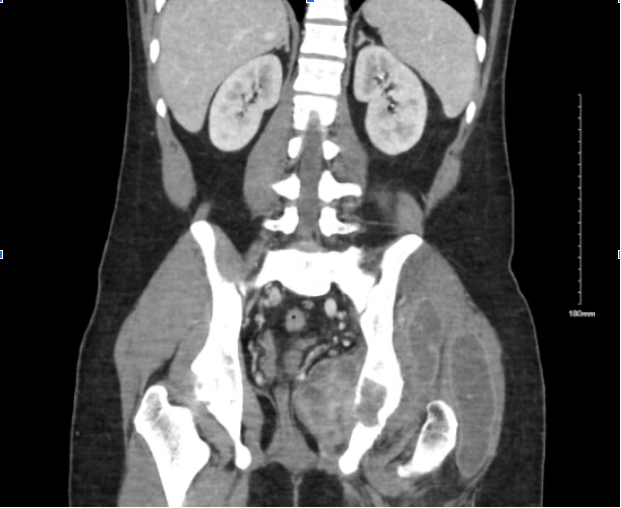

Case Presentation: A 22-year-old Filipino man presented with worsening left groin and hip pain 2 weeks after falling down 3 steps on subway stairs. Since the fall, he had minimal range of motion due to pain and required assistance with ambulation. He also reported intermittent dull achiness in that hip one week prior to the fall. On exam, he was afebrile and had severely reduced range of motion in the left hip. There was no swelling or erythema over the hip. Labs were significant for white cell count of 15,000/mcL, ESR of 64 mm/hr, and CRP of 102 mg/L. CT scan of the hip showed a 4.5 cm lytic lesion of the posterior acetabulum along with osteopenia and multiple soft tissue masses in the region surrounding the left hip. Upon further questioning, the patient reported having night sweats and subjective fevers for the past month. The presence of a lytic lesion in an otherwise young healthy man raised concern for a malignant or infectious etiology. The joint space was aspirated, draining purulent fluid which initially showed significant lymphocyte predominance and increased LDH, but AFB cultures were negative and no organisms were seen. Quantiferon test was positive, but the patient did not have pulmonary symptoms and had a clear chest X-ray. The patient was started on empiric antibiotics targeted at a pyogenic process while work-up was ongoing for other potential etiologies. Further fluid analysis revealed significantly elevated Adenosine Deaminase. Subsequently, Mycobacterium Tuberculosis PCR of the fluid confirmed tuberculosis of the joint. The patient was started on rifampin, isoniazid, pyrazinamide, and ethambutol for acetabular tuberculosis and discharged with outpatient ID follow-up.